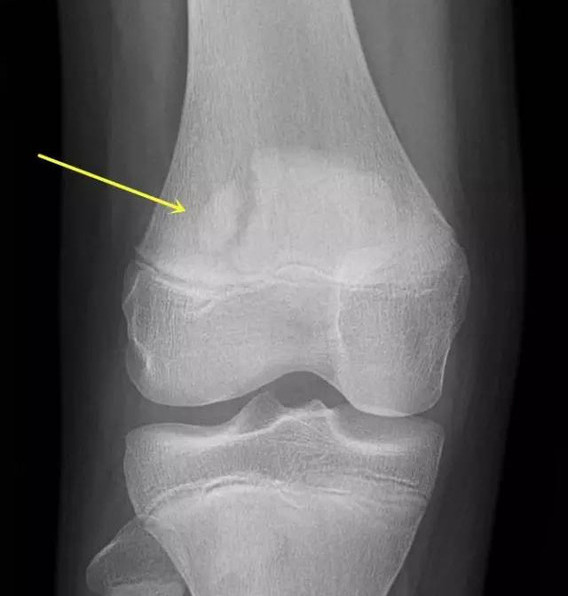

今天要为大家介绍的,是发生在膝关节髌骨,也叫波楞盖儿上的,貌似骨折的一种假骨折。也就是说,有部分人的髌骨本来就是裂开的两瓣,叫“二分髌骨”。这种二分髌骨,很多人是没有症状的,不去拍片子,本人可能永远都不会知道,因为你自己是摸不出来的。但是,有时候这种二分髌骨会引起膝关节的疼痛,叫“疼痛性二分髌骨”。

接下来,我们大家就一起来了解一下,这种颇具有迷惑性的“二分髌骨”。首先,从概念上讲,“二分髌骨(bipartite patella,BP) ”是部分人群在发育阶段由于某些因素的干扰出现的髌骨骨化异常——也就是发育过程中就没有像正常人群那样,长成一块完整的骨块,而是自然形成了两块。二分髌骨是一种解剖异常,一般都是没有症状的,而在剧烈活动、大运动量的体育训练后出现了疼痛不适,变成疼痛性二分髌骨( painful bipartite patella,PBP)。

Saupe教授,根据副髌骨一般出现的位置,将二分髌骨分为3型:I型骨化核位于髌骨下极;Ⅱ型位于髌骨外侧;Ⅲ型位于髌骨外上角,其中Ⅲ型最为多见。也就是说,分离的那小块髌骨很少会出现在髌骨的内侧,往往是出现在髌骨的下方,外侧或外上位置,尤其是外上部位。这对于我们通过X线判断二分髌骨有重要的参考意义。